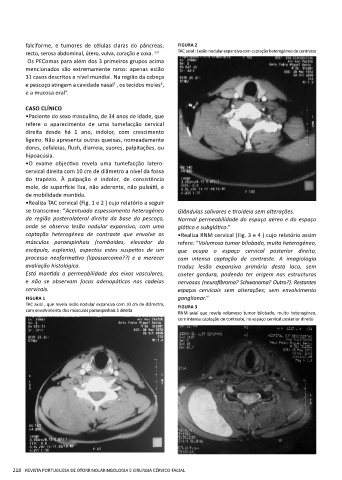

falciforme, e tumores de células claras do pâncreas, FIGURA 2

recto, serosa abdominal, útero, vulva, coração e coxa. 1-3 TAC axial : Lesão nodular expansiva com captação heterogénea de contraste

•Realiza TAC cervical (Fig. 1 e 2 ) cujo relatório a seguir

se transcreve: “Acentuado espessamento heterogéneo Glândulas salivares e tiroideia sem alterações.

da região posterolateral direita da base do pescoço, Normal permeabilidade do espaço aéreo e do espaço

onde se observa lesão nodular expansiva, com uma glótico e subglótico.”

captação heterogénea de contraste que envolve os •Realiza RNM cervical (Fig. 3 e 4 ) cujo relatório assim

músculos paraespinhais (romboides, elevador da refere: “Volumoso tumor bilobado, muito heterogéneo,

escápula, esplenio), aspectos estes suspeitos de um que ocupa o espaço cervical posterior direito,

processo neoformativo (lipossarcoma??) e a merecer com intensa captação de contraste. A imagiologia

avaliação histológica. traduz lesão expansiva primária desta loca, sem

Está mantida a permeabilidade dos eixos vasculares, conter gordura, podendo ter origem nas estructuras

e não se observam focos adenopáticos nas cadeias nervosas (neurofibroma? Schwanoma? Outro?). Restantes

cervicais. espaços cervicais sem alterações; sem envolvimento